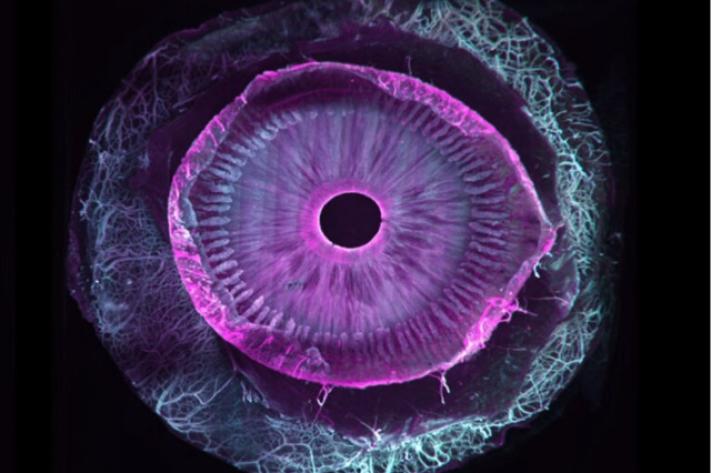

Une équipe de recherche franco-suisse est parvenue à rendre entièrement transparent un œil humain entier. Une prouesse technique qui va permettre aux scientifiques du monde entier de mieux étudier les maladies des yeux et leurs mécanismes.

Sept ans de travail pour une première mondiale : la transparisation (le fait de rendre transparent) d’un œil humain entier. Ce travail, tout juste publié dans la revue Communications Biology, est une collaboration franco-suisse entre, d'une part, Marie Darche, une ingénieure de recherche et membre de l’équipe du Pr Michel Paques à l'hôpital des Quinze-Vingts et à l’institut de la vision (Paris), et d'autre part ses collègues de l’institut Wyss (Genève).

Si les seconds se sont eux occupé du versant imagerie du projet grâce à un dispositif optique particulier, un microscope à feuillet de lumière (MesoSPIM), la biologiste s’est, elle, attaquée au versant "clearing", c’est-à-dire les étapes de transparisation permettant de transformer un échantillon biologique initialement opaque en une structure transparente. Comment ? Par différentes manipulations reposant sur une succession de bains dans des solvants organiques associées au marquage par des anticorps fluorescents.

Tout commence forcément avec des dons d’yeux, issus ici de donneurs américains morts, la législation française ne permettant pas ce type précis de dons (la banque française des yeux ne s’occupe que des cornées et pas d’œil entier). En pratique, toujours de petites sphères de six centimètres cube de volume, dont on ne soupçonne pas l’extraordinaire complexité ni l’hétérogénéité en lien avec les différentes couches de cellules, vaisseaux, nerfs, cellules immunitaires…

Car si d’autres équipes étaient parvenues par le passé à clarifier certains segments de l’œil, c’est bien ici la première fois qu’un œil entier est transparisé. "Au total, nous avons utilisé 25 yeux sains et allons prolonger nos travaux avec d’autres globes oculaires cette fois pathologiques et atteints de DMLA (dégénérescence maculaire liée à l'âge, ndlr), de glaucome et de myopie forte, le tout grâce au soutien d’associations de patients", précise la chercheuse, qui poursuit : "Nos travaux permettront une approche plus holistique des pathologies de l’œil tout comme un meilleur dialogue entre chercheurs et cliniciens pour mieux comprendre les maladies de l'œil et leurs mécanismes".L’équipe a déjà prévu de partager ses images en open source avec l’ensemble de la communauté scientifique et envisage au sein de l’hôpital des Quinze-Vingts l’acquisition de son propre microscope à feuillet de lumière. Semblable à celui situé à Genève, il pourrait toutefois disposer de nouvelles possibilités (plus de zoom, plus de couleurs...), histoire de voir toujours plus loin.